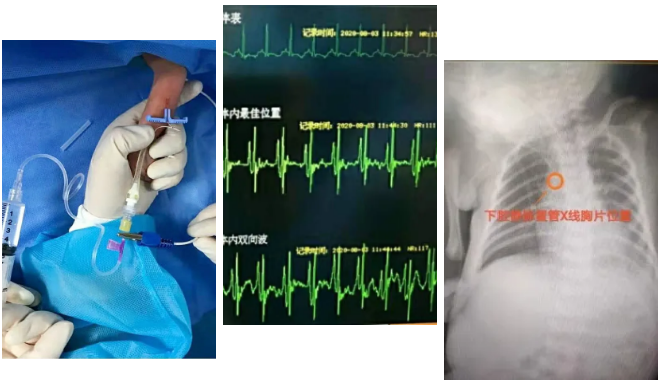

为了提高新生儿PICC置管技术成功率和安全性,徐丽容护士长又开展了PICC置管心电定位技术,成功利用心电波形引导穿刺,精确定位。该技术的开展,填补了从化区在此项技术上的空白。

这3名宝宝是新生儿科收治病人中体重最低、胎龄最小的,必须及时给小宝宝通过静脉用药和供给营养,徐丽容护士长决定为患儿经外周静脉置入中心静脉导管(简称PICC),由于患儿手臂只有成人的食指粗细,而且还有轻度水肿,给置管增加了不小的难度,徐丽容护士长细心研究,反复和团队论证穿刺方法,在她的努力下,小宝宝一次穿刺就成功置管,得到了及时救治。